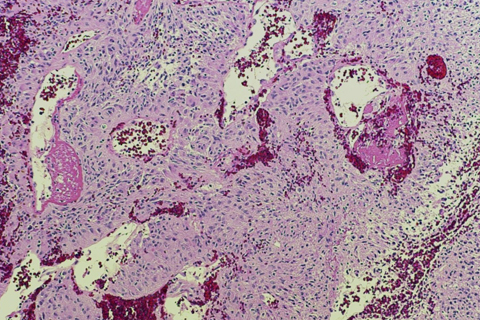

- To recognize neoplastic, non-tumorous and low-grade neuropathologic lesions and potential misdiagnosis

This one-month rotation includes an initial introduction to normal anatomy of the neuromuscular system, with subsequent weeks focused on CNS neoplasms, diseases of the muscles and nerves, and vascular, demyelinating, infectious and neurodegenerative disorders. Review of neuroimaging and correlation with the pathology is an integral aspect of the rotation. There is a comprehensive study set for review of all important neuropathologic lesions in addition to daily case review.